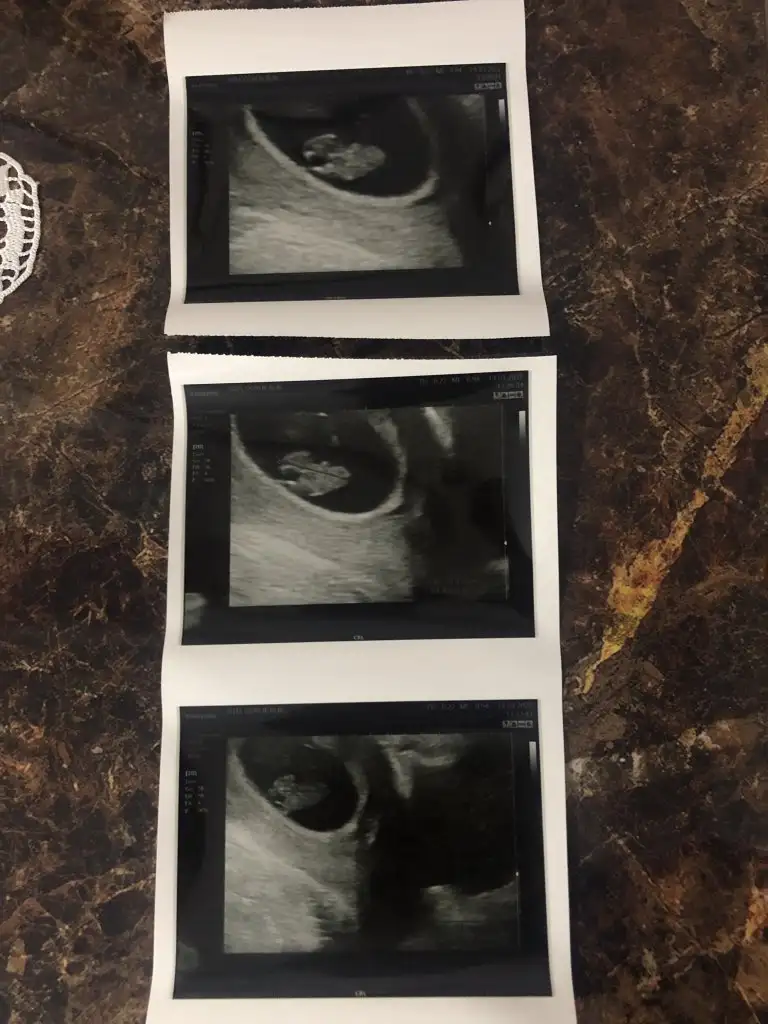

Kız bence7 hafta 4 gunluk vajinal muane ile bakildi acaba tahminde bulunabilirmisiniz.